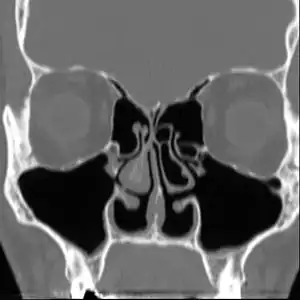

Empty nose syndrome (ENS) is a clinical syndrome, the hallmark symptom of which is a sensation of suffocation despite a clear airway. This syndrome is often referred to as a form of secondary atrophic rhinitis. ENS is a potential complication of nasal turbinate surgery or injury.[1][2] Patients have usually undergone a turbinectomy (removal or reduction of structures inside the nose called turbinates) or other surgical procedures that injure the nasal turbinates.

The condition is caused by injury to the nasal turbinates, particularly with nasal procedures. This includes both minor procedures as well as total turbinate resection. It is usually observed in patients with unobstructed nasal passages following surgical intervention who report sensations of suffocation or obstruction following recovery. Early literature attributed ENS to complete turbinate resection, but later research demonstrated the syndrome in patients who had undergone a range of procedures that involved nasal turbinates.[3][5][6][7][8]